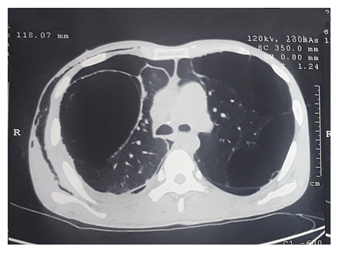

Chest X-ray PA view revealed bilateral large lucent areas with mediastinal shift and the largest one in the right upper thorax. (Figure 1) CECT Chest was performed then, which showed giant bullae occupying left and right upper lobes, with the largest one measuring 13 x 12 x 10 cm on right side (Figure 2).

Figure 2 CECT Chest showing distorted lung parenchyma with formation of large bullae in both upper lobes, largest measuring 13x12x10 cm at right side.